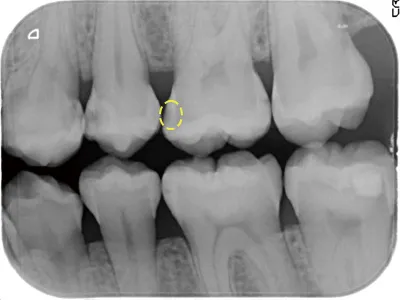

写真3 穴があいている(黄色の破線の円))

写真3は、たとえ歯に穴があっても、非修復治療によって、むし歯をコントロールしています。穴を歯科用材料で詰めるとなると、健康な歯の部分も余分に削らないと、詰めたものがすぐに外れます。

写真4 2011年12月撮影

写真4から写真5は、なんと10年以上もむし歯が進行していません。たとえむし歯が象牙質に進行(歯に穴が空いている)していても、非修復治療で、進行を止めることができるのです。